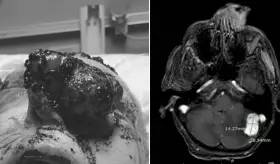

La gota es una enfermedad sistémica que puede afectar diferentes partes del cuerpo debido a la acumulación de urato monosódico en los tejidos.